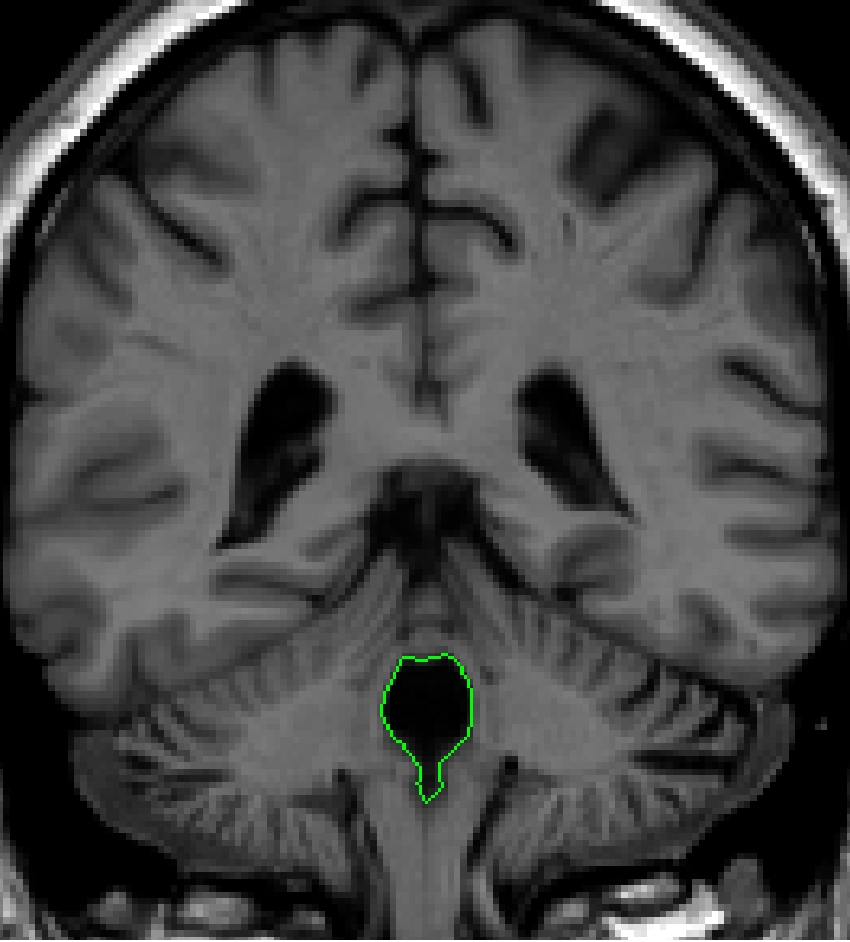

Part IV - fourth ventricle in the cerebellum

When

the fourth ventricle is no longer surrounded by brainstem, it appears between

cerebellum gray and white matter. Two histograms should be used for this

outline: one between the CSF and the cerebellum white matter, and the second

between the CSF and cerebellum gray matter.

In its most posterior extent, the fourth ventricle will appear as two separate

circles in each cerebellar hemisphere. The most accurate means to extract these

structures is to do two separate histograms for each cerebellar hemispheres

(CSF - white matter; CSF - gray matter). As with the most anterior extend of

the 4th ventricle, modifying this

estimate with the contour line may be necessary.